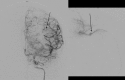

Traumatic intracranial pseudoaneurysms are a rare but severe complication following arterial injury. Pseudoaneurysm formation can occur secondary to blunt or penetrating trauma or iatrogenic injury. We report a case of traumatic pseudoaneurysm secondary to placement of an intracranial pressure (ICP) monitor. A 27-year-old man was involved in a motorcycle accident resulting in multiple intracranial hemorrhages. The patient underwent craniectomy and placement of an ICP monitor. 17 days later he developed dilation of his left pupil, with imaging demonstrating a new hemorrhage in the vicinity of the previous ICP monitor. A cerebral angiogram confirmed a left-sided distal M4 pseudoaneurysm which was treated by n-butyl cyanoacrylate embolization. Intracranial pseudoaneurysm formation following neurosurgical procedures is uncommon. Delayed intracranial hemorrhage in a region of prior intracranial manipulation, even following a procedure as 'routine' as placement of an ICP monitor, should raise the suspicion for this rare but potentially lethal complication.